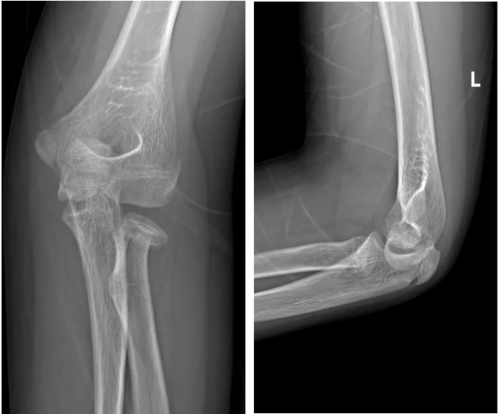

不久前,小杰在学校运动时不慎摔倒,左肘部瞬间剧痛、无法活动,家属紧急将其送至我院骨科。经影像学检查,小杰被确诊为 “左桡骨颈骨折”,桡骨颈位于肘关节桡骨近端,骨折后若处理不当,可能影响前臂旋转功能及肘关节发育,这对实施手术要求较高。

术前X片见桡骨颈成角移位

图片6.png

▲术后复查X线片显示:桡骨颈骨折解剖复位,内固定位置理想